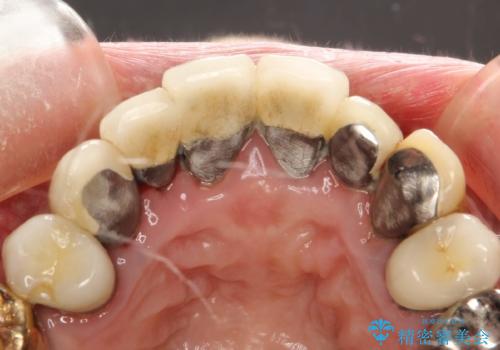

・虫歯がとりきれていない

・接触部分がガタガタで適合の悪い金属

・全く無菌の努力がされていない根管治療

など、いい加減な治療は「治療」ではなく、むしろ医原性に歯の寿命を短くします。

最もよくないのは、クオリティの低い治療を何度も繰り返すことです。